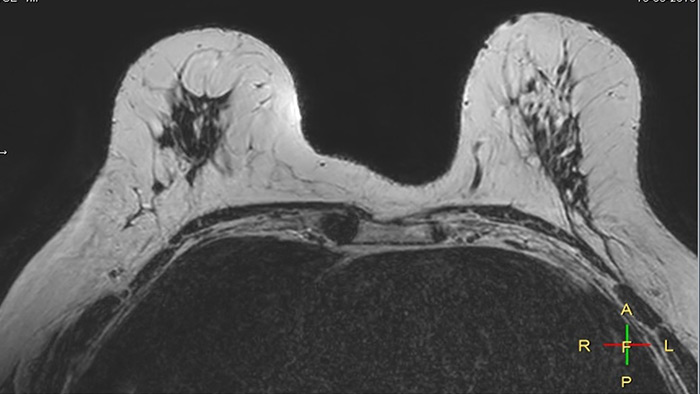

Compressed SENSE 3:54 min

Compressed SENSE, scan time 3:54 min

C-SENSE factor 12

Voxels acq 0.8 x 0.72 x 1.8 mm

Voxels recon 0.63 x 0.63 x 0.9 mm

SENSE 6:32 min

SENSE, scan time 6:32 min

SENSE factor 3

Voxels acq 0.8 x 0.8 x 1.8 mm

The time gain with Compressed SENSE was also used to increase resolution in order to help radiologists identify the tumor characteristics more confidently which may be used for a more personalized treatment. For example, in breast imaging, resolution is crucial for visualization of very small lesions. Compressed SENSE allows to scan thinner slices, allowing a 3D isotropic sequence which can provide increased diagnostic confidence for the radiologists.

Breast

6:32 min

3:54 min

2:38 min [40%]